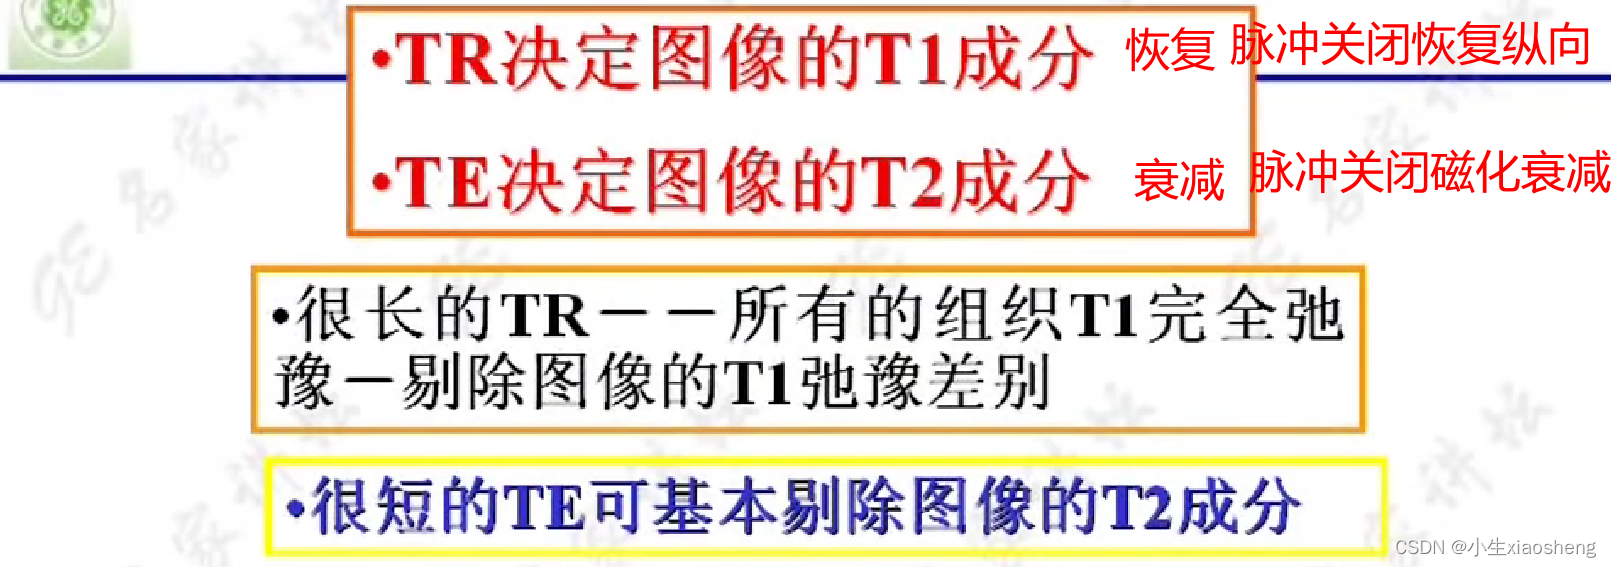

选择合适长的TE获得最好的T2对比:一般TE选择两种组织生物T2值附近可获得最好的T2对比。

选择合适短的TR获得最好的T1对比:一般TR选择两种组织生物T1值附近可获得最好的T1对比。